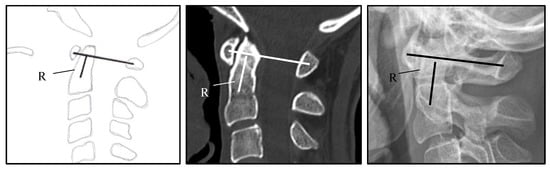

| CS (Cranial Settling) | vertical translocation of dens into the foramen magnum | see Figure 1 and Figure 2 |